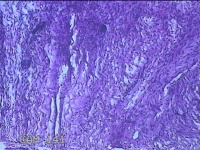

右侧卵巢囊肿

性别

女

年龄

19岁

临床诊断

一般病史

下腹痛1小时。

标本名称

大体所见

灰白暗红色囊壁样组织11x4.5x2.3cm两块,表面糜烂,因已切开,囊内容物已流失,囊壁厚0.1cm。